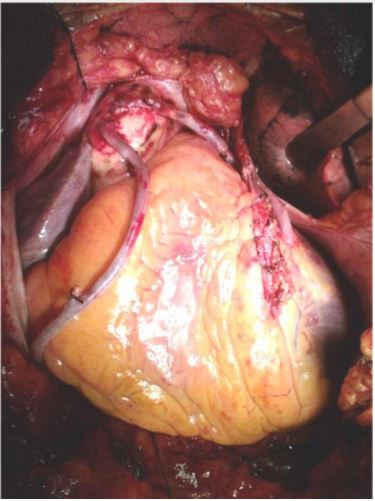

Em relação a imagem abaixo, é correto afirmar: